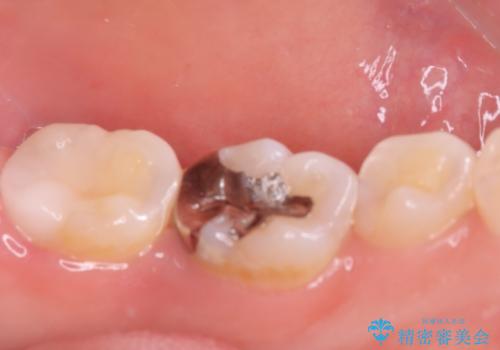

- 初診時にお口の中をチェックしたところ虫歯があり、大きさから部分的な詰め物のお話をしました。材料の特性を説明し、再び虫歯になりにくいセラミックインレーを選択されました。

セラミックインレー接着時にはラバーダム防湿を行いました。